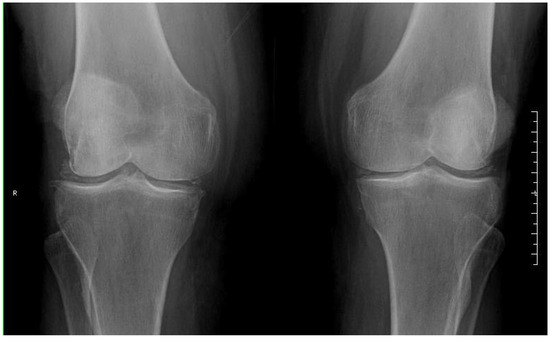

2. Detailed Case Description